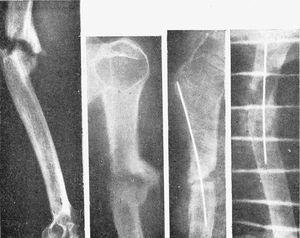

Figura 9. Pseudoartrosis tercio medio húmero. Después del refrescamiento de fragmentos se intentó enclavijamiento con tallo de Küntscher, fracasando por la osteoporosis de todo el húmero. Se hizo un enclavijamiento con alambre y un relleno con papilla ósea, consiguiéndose la consolidación.

Figura 11. Complicación que se produce por no seleccionar bien el diámetro del clavo; astillamiento del fragmento proximal.

Figura 12. Otra complicación de enclavijamiento cerrado; el fragmento proximal estallado ha sido penetrado por el distal en cuña al impactar; el control radiográfico puso en evidencia el accidente y hubo que retirar el tallo y reducir la penetración; curó sin complicaciones.